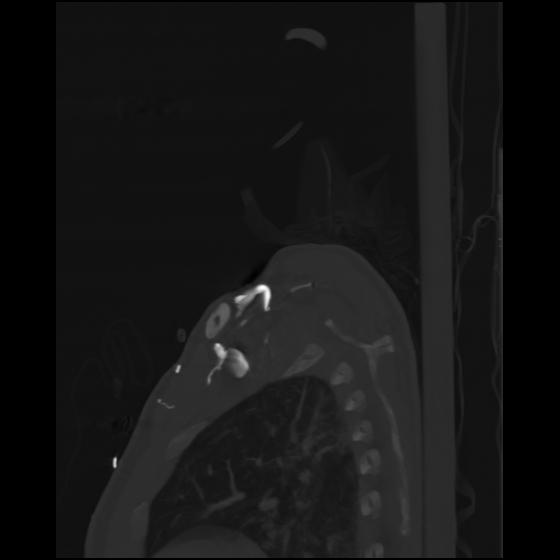

24 ANGIO,CE,Sag-MIP,5.000,ANGIO,Sag-MIP,